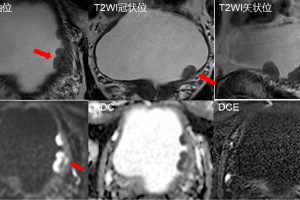

精准“照妖”,揪出早癌——特异性对比剂钆塞酸二钠投入临床应用

在肝脏疾病的诊断中,早期发现、精准定性是治疗成功的关键。我院医学影像部现已常规开展肝胆特异性磁共振对比剂——钆塞酸二钠检查技术,为肝脏占位的鉴别诊断开启“高清模式”。